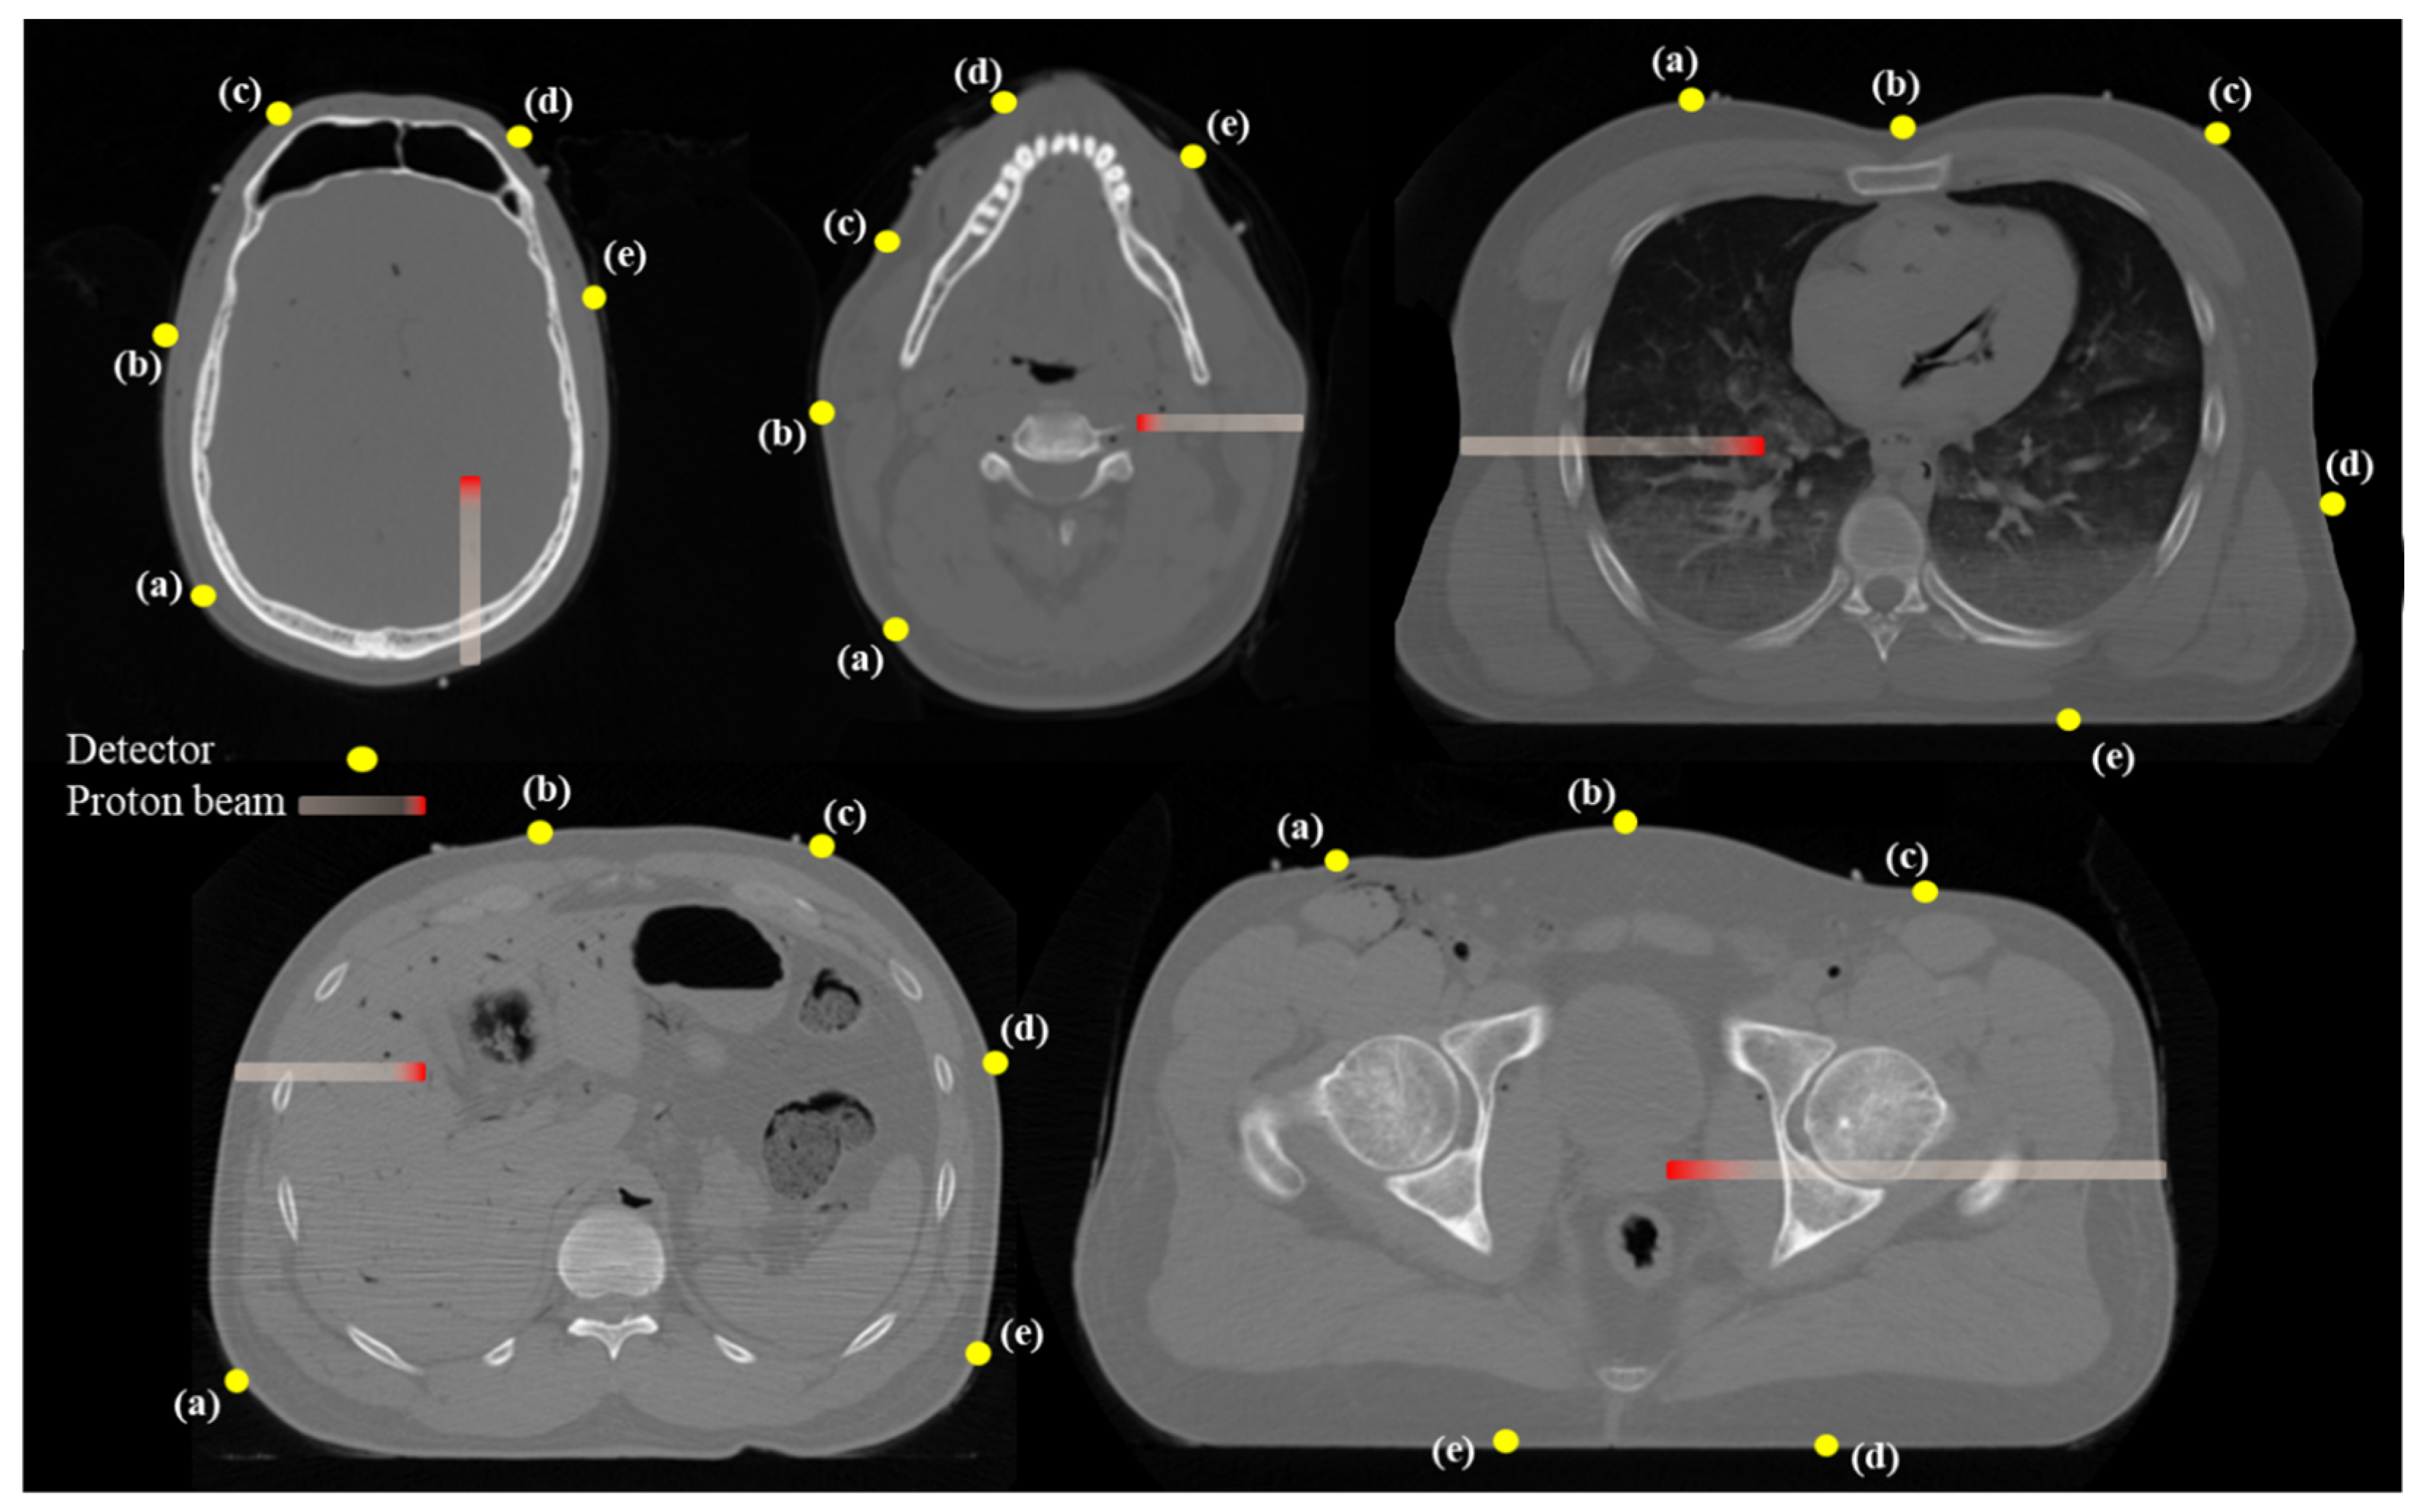

2.2.3. Appropriate Detector Positioning Based on Clinical CT Cases

3.3. Appropriate Detector Positioning Based on Clinical CT Cases

4.3. Clinical Feasibility and Detector Placement Optimization

| Treatment Case | Detector Position | |||||

|---|---|---|---|---|---|---|

| (a) | (b) | (c) | (d) | (e) | ||

| Brain | [mm] | 94.7 | 111.14 | 141.03 | 116.5 | 74.65 |

| [mm] | 93.97 | 112.97 | 249.15 | 171.678 | 91.19 | |

| [mm] | 0.73 | 1.83 | 108.12 | 55.18 | 16.54 | |

| [%] | 0.77 | 1.65 | 76.66 | 47.36 | 22.16 | |

| Head & Neck | [mm] | 104.66 | 99.02 | 93.01 | 100.22 | 72.8 |

| [mm] | 189.52 | 112.76 | 130.86 | 115.15 | 103.34 | |

| [mm] | 84.86 | 13.74 | 37.85 | 14.93 | 30.54 | |

| [%] | 81.08 | 13.88 | 40.69 | 14.90 | 41.95 | |

| Liver | [mm] | 130.6 | 134.62 | 215.18 | 265.19 | 282.18 |

| [mm] | 143.14 | 107.94 | 296.83 | 282.79 | 331.46 | |

| [mm] | 12.54 | 26.68 | 81.65 | 17.60 | 49.28 | |

| [%] | 9.60 | 19.82 | 37.94 | 6.64 | 17.46 | |

| Prostate | [mm] | 163.03 | 121.02 | 127.26 | 132.97 | 130.38 |

| [mm] | 202.09 | 117.63 | 90.35 | 121.63 | 172.1 | |

| [mm] | 39.06 | 3.39 | 36.91 | 11.34 | 41.72 | |

| [%] | 23.96 | 2.80 | 29.00 | 8.53 | 32.00 | |

| Lung | [mm] | 130 | 143.69 | 241.05 | 252.56 | 182.22 |

| [mm] | 95.71 | 175.28 | 322.37 | 444.95 | 245.62 | |

| [mm] | 34.29 | 31.59 | 81.32 | 192.39 | 63.40 | |

| [%] | 26.38 | 21.98 | 33.74 | 76.18 | 34.79 | |